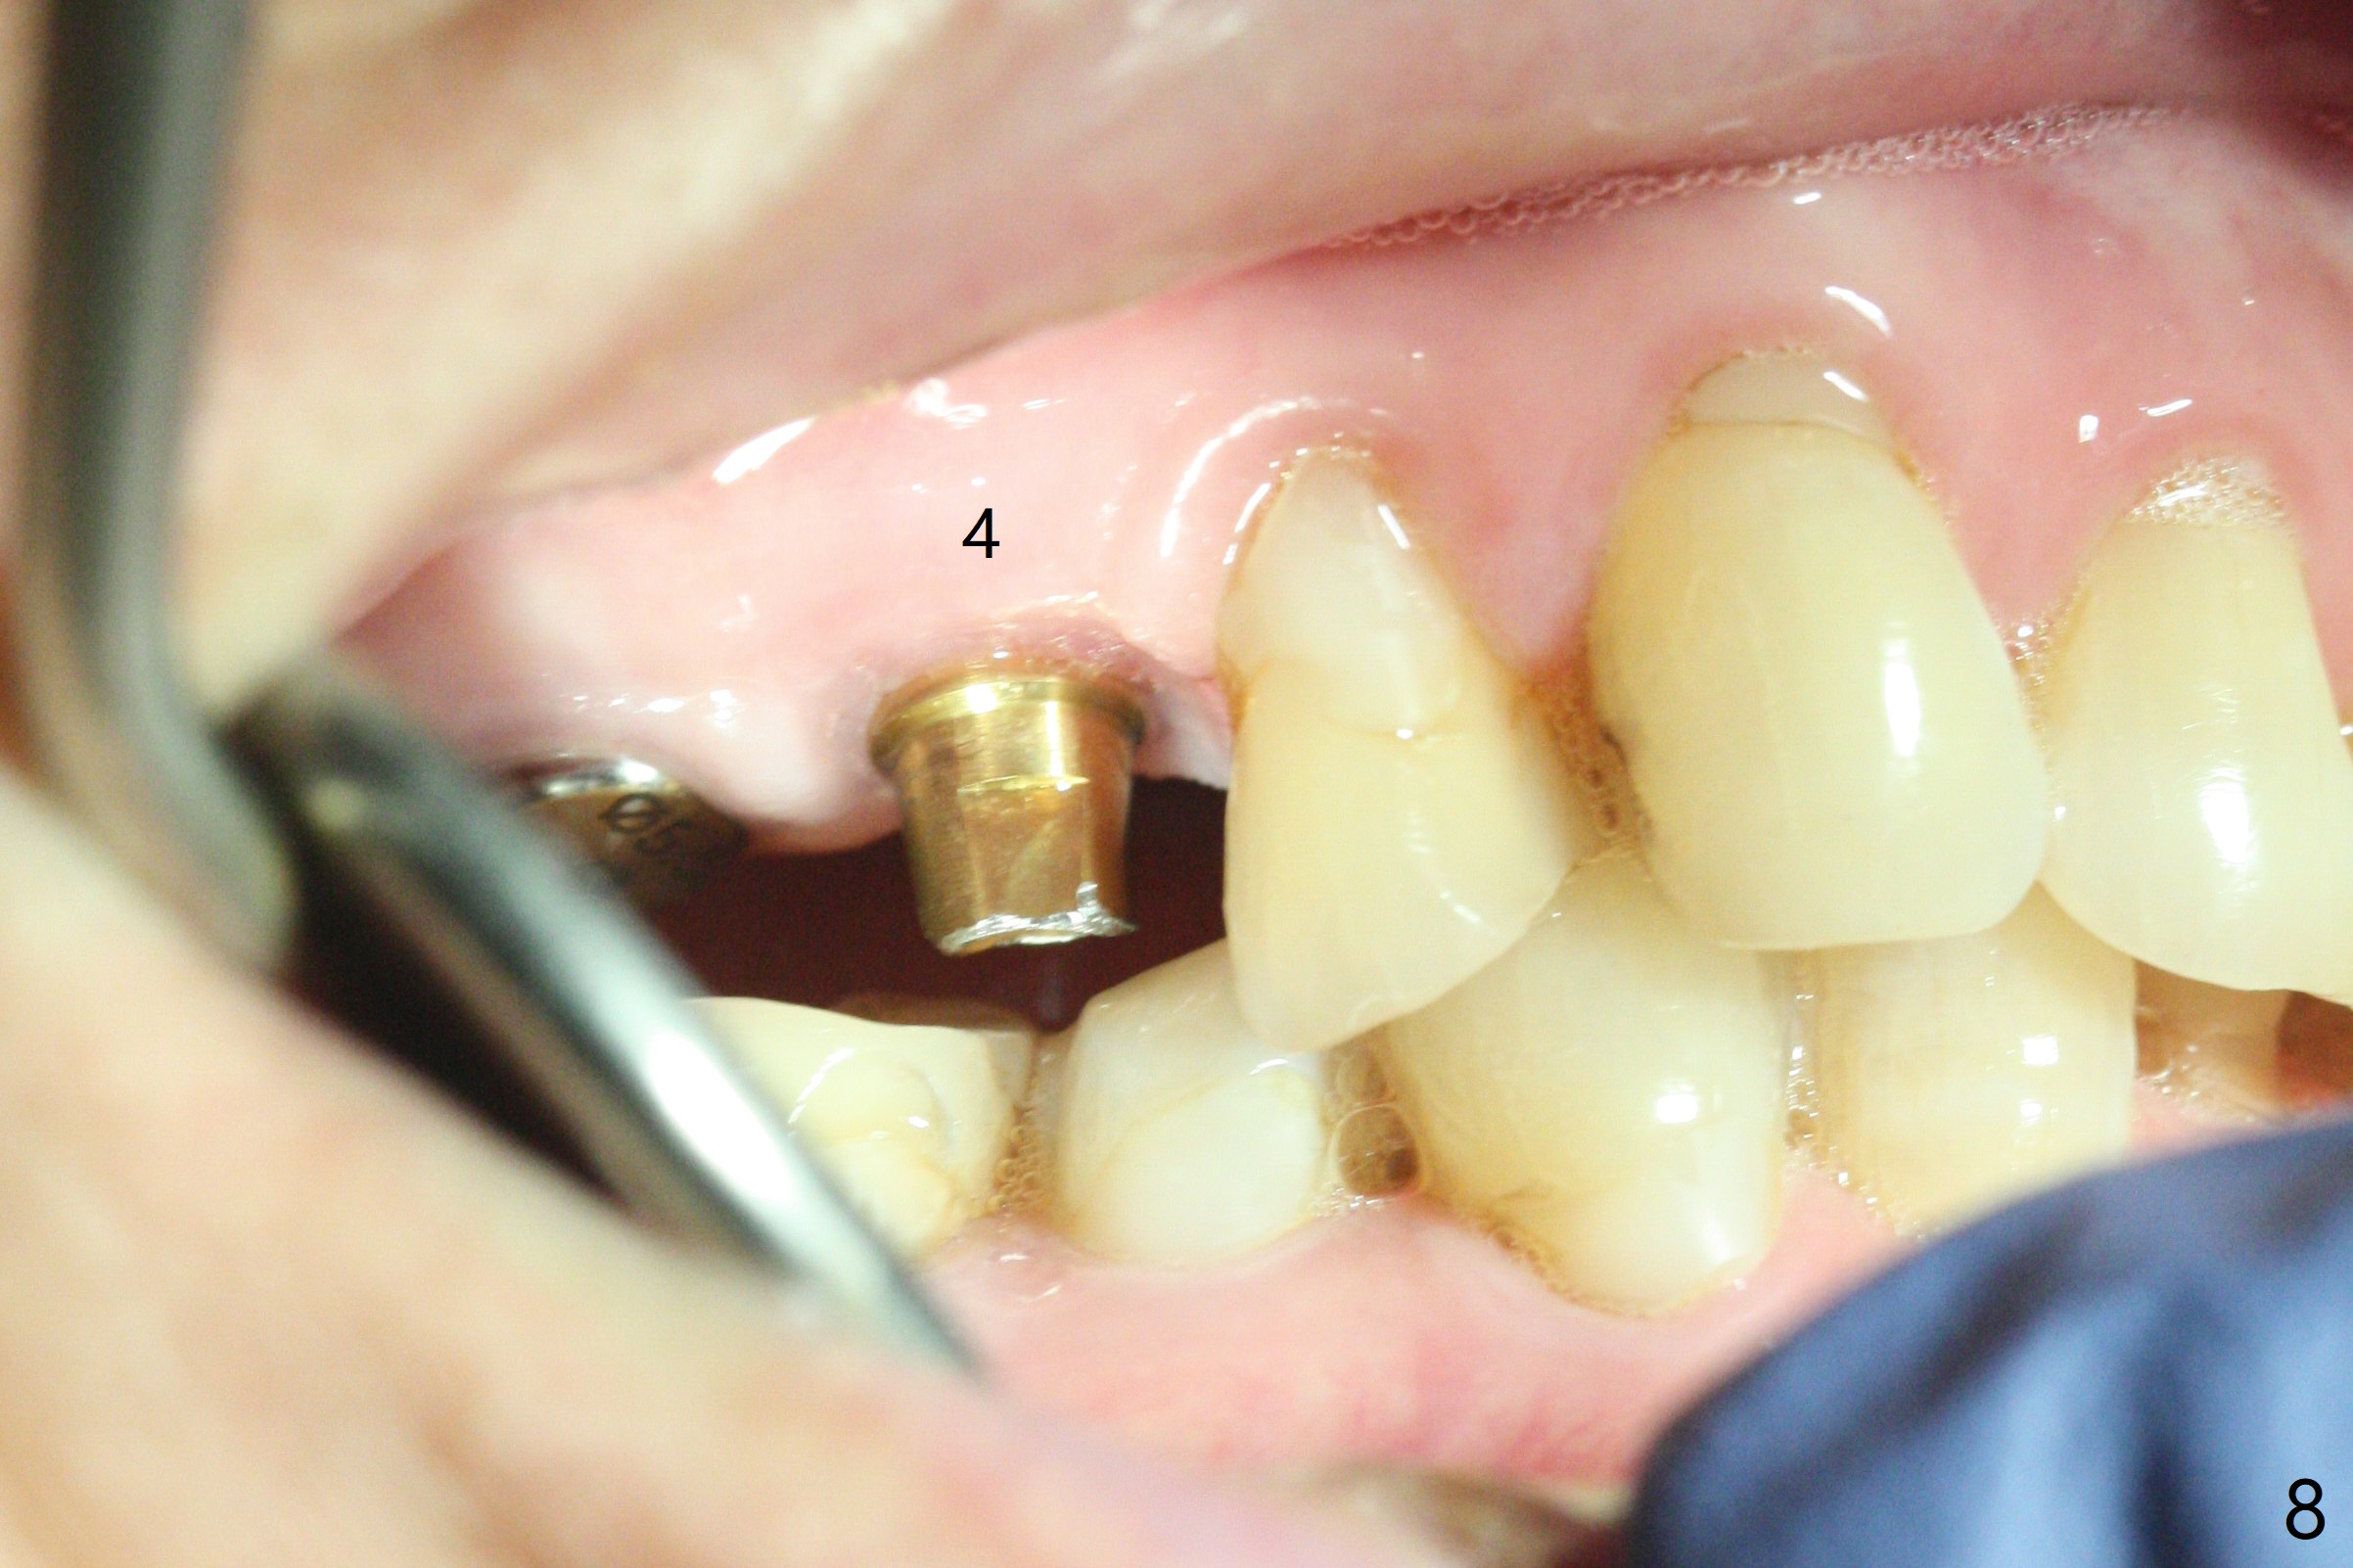

Osteotomy at #3 is performed last (Fig.1,2); as planned, a 4 mm cortical tap is used with guide for sinus lift. Unfortunately the sinus membrane is perforated. Implant placement is aborted. Instead Osteogen plug is inserted into the osteotomy, which is fixed in place by acrylic extending from the provisional at #4. Osteotomy for #3 implant will be attempted with control of the depth in 4 months. The patient has allergy to Amoxicillin (rash). When switching to Clindamycin, she develops diarrhea and loses 10 pounds. There is no abnormality at the site of #3 or 4 nearly 3 months postop (Fig.3). The next surgery will be most likely conducted without antibiotic 4 months postop. Try to draw blood for PRF. Take PA for #12 and 13 for possible impression. Remove the 3 temporary crowns, seat the guide across the arch and use no-stop fixture mounts at #4, and possibly 12 and 13. Follow the original drill sequence (check perforation after each drill, Fig.11) and use DIONavi sinus approach kit. Also load an appropriate stop for the round bur for sinus lift before hand. Mixture allograft with Metronidazole and PRF. In fact everything goes on as smoothly as planned. Osteotomy at #3 is underprep (3.5 mm in diameter drill instead of 4.0). The sinus floor appears to remain to be absent; 3.2 mm round bur is used for lift, alternating with water pumping. Following insertion of 3 pieces of PRF membranes and Vanilla Graft (Fig.4 *), a 4x10 mm dummy implant is placed. After additional bone graft (Fig.5 *), a final 4.5x7.3 mm implant is placed ~10 Ncm. The implant is placed deeper ~ 1 mm, followed by a 5.5x3 mm healing abutment (Fig.6). The implants at #12 and 13 seem to have osteointegrated (Fig.7). Impression is taken for #4, 12 and 13 with limited vertical space (Fig.8,9). An implant at #14 is being considered. There is faint bone graft around the apex of the implant 4 months postop (Fig.10). The implant sustains 25-30 Ncm torque when a 5.2x4(3) mm cemented abutment is placed. A permanent crown is cemented nearly 5 months postop (Fig.11). For the best cosmetic and masticating results, the occlusal surface should have certain degree of morphology, such as the buccal cusps (Fig.12 white curved lines). The abutment at #3 is placed and torqued to 30 Ncm before re-cementation of the repaired crown (increased occlusal surface contact). In fact the abutment at #4 is incompletely seated with a gap (Fig.13 <). The composite at #5 is dislodged while #3 crown is being repaired (*). The abutment at #4 is loose >1 year post cementation. The abutment remains incompletely seated (gap and longer apical space (double arrows)) when the abutment/crown complex rotates lingual mesiobuccal (Fig.14 curved arrow). Further proximal reduction and lingual rotation distobuccal leads to complete seating (Fig.15). It appears that incomplete seating at #13 is associated with hex mismatch (Fig.16, large apical space), which will be fixed next visit. One week later, the crown and abutment of #4 are seated together after crown repair (Fig.17). Since the abutment margin is subgingival, the crown is cemented, removed with abutment for residual cement removal and reseated with the abutment with torque at 30 Ncm. After this, the crown and abutment of #13 is reseated after mesiobuccal surface is trimmed (Fig.18), followed by pick up impression. A few days later, the crown/abutment are inserted together smoothly, the former cemented and the complex unscrewed for residual cement removal and last torqued at 30 Ncm without any X-ray confirmation.